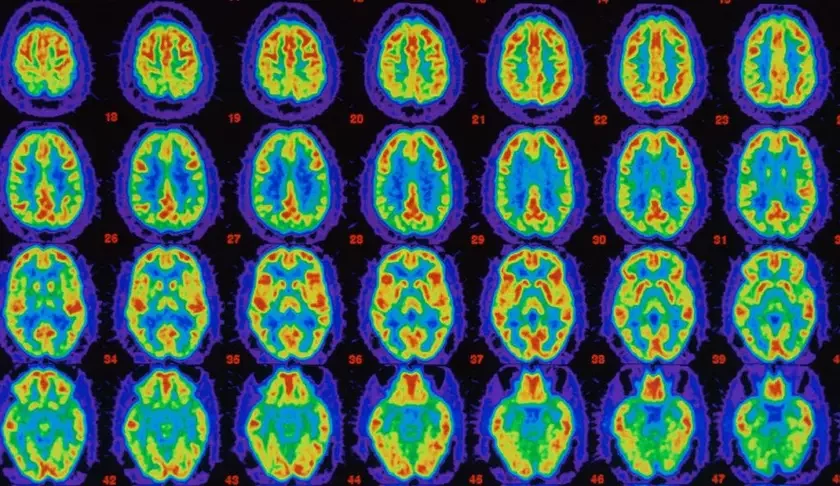

Чтобы установить это, мы с коллегами использовали технику визуализации мозга для группы здоровых женщин среднего возраста. Это позволило нам измерить нейронную активность и присутствие бляшек Альцгеймера. Тесты показали, что женщины, которые были в постменопаузе, имели меньше активности мозга и больше бляшек Альцгеймера, чем женщины в пременопаузе. Еще более удивительно, что это было также и у женщин с перименопаузой — у тех, кто только начинал испытывать симптомы менопаузы. И мозг обеих групп показал еще более резкие различия по сравнению с мозгом здоровых мужчин того же возраста.

Хорошей новостью является то, что по мере того, как женщины достигают 40 и 50 лет, оказывается, есть окно возможностей, когда можно обнаружить ранние признаки более высокого риска Альцгеймера — сделав тест с визуализацией мозга, как мы это делали, — и принять действия по снижению этого риска.